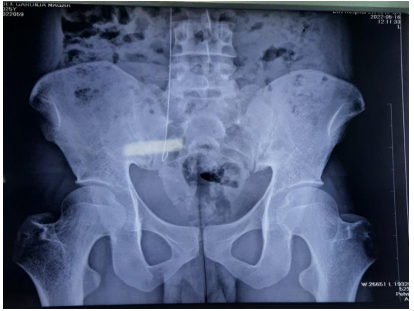

A 25 years old male with hypertension and CKD stage IV presented in the emergency with acute gastroenteritis, acute kidney injury and pulmonary edema due to fluid overload for which urgent hemodialysis with internal jugular vein hemodialysis catheter was planned. Resident Doctor of Internal Medicine performed the catheterization. After completing the catheterization, flow through each port was checked and found normal. One session of hemodialysis was also done which was uneventful. However, when a follow up chest X-ray was done, retained guidewire was identified (Figure 1). Subsequently, an abdominal X-ray was also done (Figure 2). The guidewire extended from hemodialysis catheter lumen to pelvic brim. Intravascular position of missing guidewire was confirmed with USG. An attempt to remove the guidewire by gentle pulling of the hemodialysis catheter failed to retrieve the forgotten guidewire. Therefore, a multi department meeting was conducted. Since endovascular surgery with expertise to retrieve missing guidewire was not available in our centre, consensus was made for surgical retrieval of retained guidewire.

Figure 2: Pelvic X-ray showing the guidewire extending upto pelvic brim.